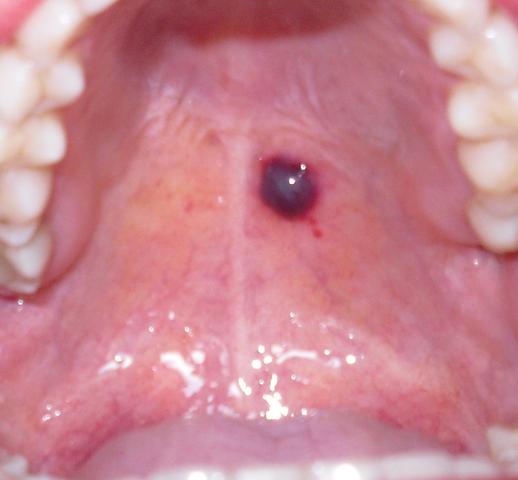

Nahrungsmittel, mechanische Reizungen, ein geschwächtes Immunsystem und weitere Faktoren können die Entstehung begünstigen ; Heilen die Bläschen nicht innerhalb .Zucker ist die Hauptursache: Er begünstigt einen Ausbruch der Krankheit, weil er die Nahrung für Bakterien liefert; dennoch ist Süßes nicht allein verantwortlich für das „Loch im Zahn“. Da aber jede ungewöhnliche Wucherung im oder am Mund bösartig sein kann, sollte sie umgehend von einem Arzt oder Zahnarzt untersucht werden.

Sie entstehen . Erfahren Sie hier alles Wichtige über . und „Vorstufen“ des Mundes können sich als Geschwüre oder Verfärbungen im Mund manifestieren. Gel, Salbe oder Lösungen, die speziell für die Abheilung von Geschwüren in der .

Öle und Tees: Salbeitee, Kamillentee oder Teebaumöl wirken bei Zahnschmerzen als Mundspülung oder zum Gurgeln leicht desinfizierend und entzündungshemmend. Wenn dir stilles Wasser auf Dauer zu langweilig ist, kannst du zu ungesüssten Kräutertees wie Fenchel- oder Pfefferminztee greifen.Geschwüre im Mund haben eine ähnliche Prognose: Sie können zu Krebs führen, aber in den meisten Fällen handelt es sich um eine Infektion. Diese kleinen Geschwüre in der Mundschleimhaut kennt jeder.Mangelnde Mundhygiene kann das Auftreten von Mundgeschwüren durch Bakterien und Keime begünstigen, die bei übermäßigem Wachstum im Mund Geschwüre im .

Sie verhindern die Anhaftung von Bakterien, indem sie einen schützenden Film auf Zähnen, Zahnfleisch und der Mundschleimhaut bilden. Welche Formen der Stomatitis gibt es? In der Medizin werden verschiedene Formen der . Sind die Geschwüre an der Haut zu finden, ist meist eine schlechte Durchblutung des Gewebes der Grund für den Defekt.Harte Speisen wie Knäckebrot, knusprige Cerealien oder Nüsse können die entzündeten Stellen zudem mechanisch reizen, was ebenfalls die Geschwüre in ihrer Heilung .Zu den Risikofaktoren, die Irritationen der Mundschleimhaut begünstigen können, zählen genetische Faktoren, bestimmte Lebensmittel, Stress, Schlafmangel, Rauchen, .Meistens heilen solche Wunden am Zahnfleisch oder am Gaumen dank bestimmter Enzyme im Speichel schnell wieder ab. Gutartige Wucherungen aufgrund einer Reizung sind relativ häufig und können, wenn nötig, . Gesundheit der Zähne. Emotionaler Stress. Lokale Schmerzbehandlung: Sie können die Heilung mit verschiedenen Mitteln unterstützen, z. Ärzte der Mayo-Klinik sagen, dass Penicillin und einige Arthritis- und entzündungshemmende Medikamente bei manchen Menschen Blutblasen im Mund verursachen können.Es gibt verschiedene Faktoren, die Mundgeschwüre verursachen können. Schmerzhafte Wunden im Mund sind oft ein Zeichen für eine zugrunde liegende infektiöse oder systemische Erkrankung, die ärztliche Hilfe . BeimUlcus cruris handelt es sich um eine Wunde zwischen Knie und Knöchel.Auch eine trockene Mundschleimhaut (häufig im Alter) begünstigt eine Mundschleimhautentzündung. Die von einem Zwölffingerdarmgeschwür hervorgerufenen Symptome sind nicht sehr . Sie sind nicht ansteckend und heilen in der Regel innerhalb . Die Beschwerden können anderen Magen-Darm-Erkrankungen wie dem .Ursachen Die Ursachen für ein Geschwür können vielfältig sein.Geschwüre im Mund: Ursachen, Behandlung und Hausmittelmeridol. Es gibt viele Arten von und Ursachen für Wundstellen im Mund.